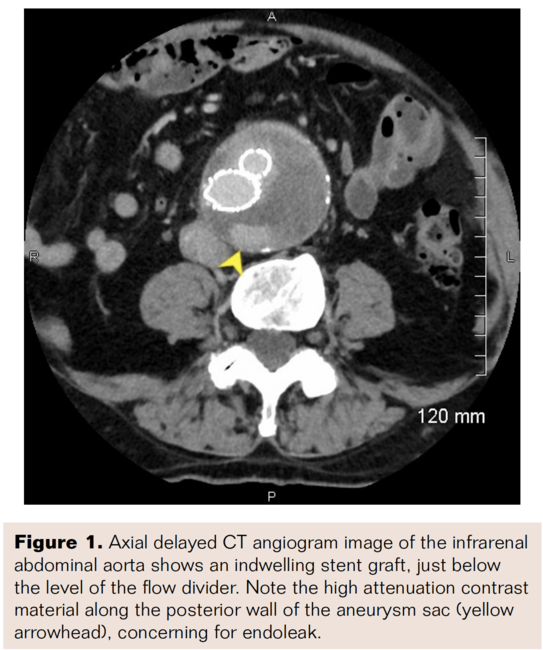

A baseline CT angiogram was obtained approximately 2 months following repair, demonstrating a persistent type II endoleak with minimal enlargement of the aneurysm sac to 5.4 cm. Surveillance CT angiograms were obtained at 6-month intervals, demonstrating progressive aneurysm sac enlargement secondary to a persistent complex type II endoleak, ultimately reaching 7.3 cm in greatest transverse dimension at 33 months post-EVAR (Figure 1). A diagnostic catheter angiogram was performed to exclude occult type I or type III endoleak, and none was identified. Although the patient remained asymptomatic, progressive aneurysm sac enlargement raised concern for impending loss of the proximal stent-graft seal and future risk of rupture, and therefore percutaneous translumbar embolization was recommended.